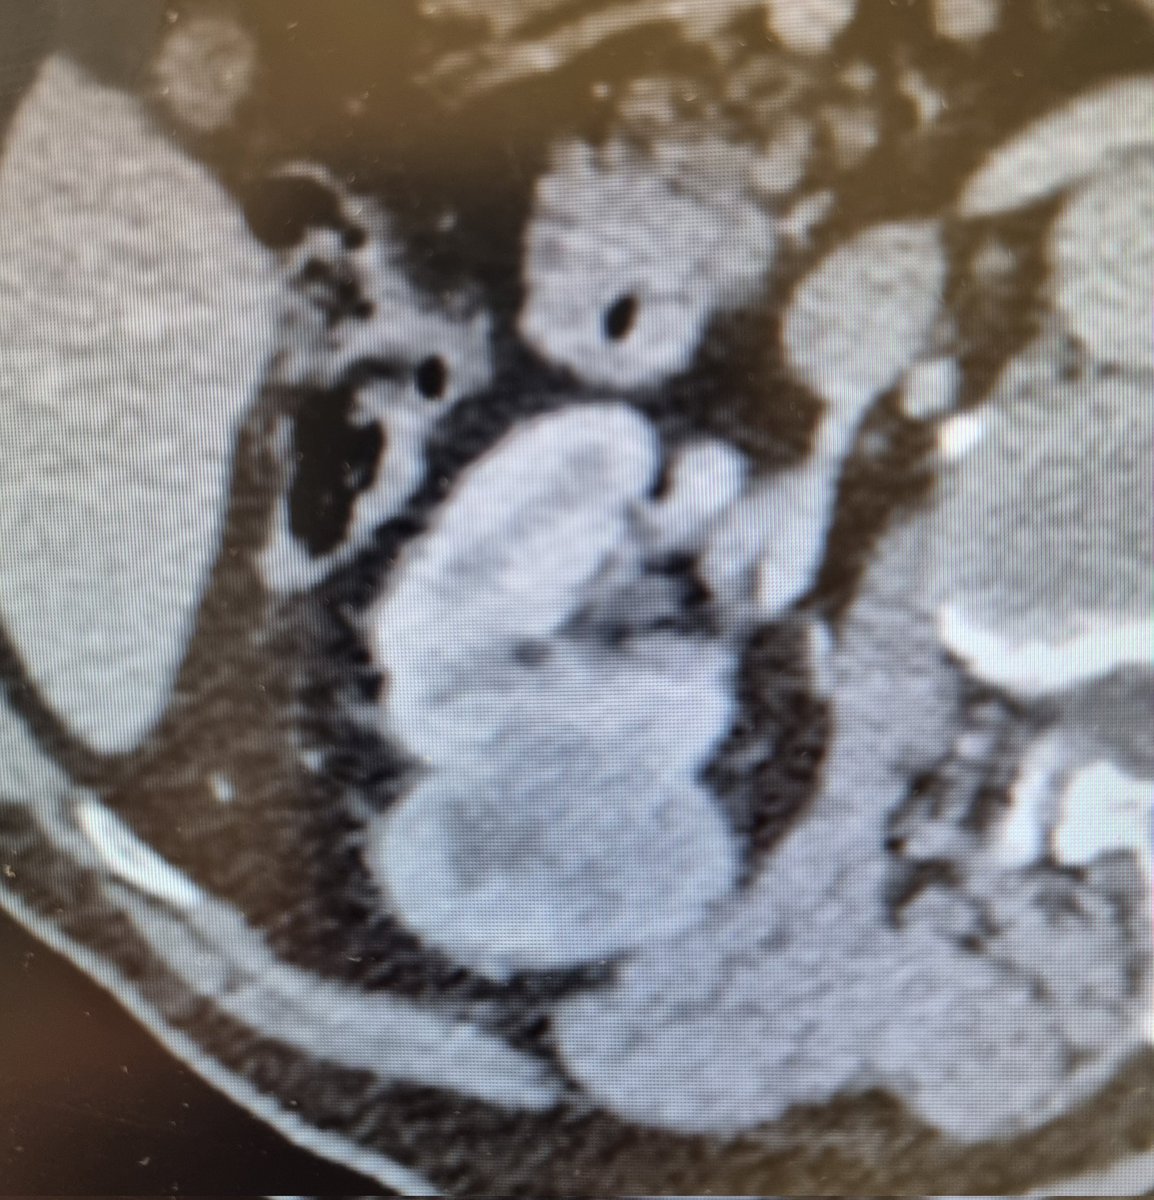

Curso de #nefrectomíaparcial robótica en #HURH Tumores sinusales endofiticos Un placer tener con nosotros a los Dres. Mario Martin y Leticia Polvorinos Gracias a @abexDaVinci por el apoyo ¡Orgulloso de mi equipo! @CoralManso

@ppalaciov

@kikegonzalez11

#RAPN

#training

Workshop on robot-assisted #retroperitoneoscopic partial nephrectomy at #HURH - endophitic T1a - T1b in single kidney Congrats to my team for the effort! @CoralManso @ppalaciov @kikegonzalez11 Thanks to @abexDaVinci for the support #teamwork

#teaching

0

5

22